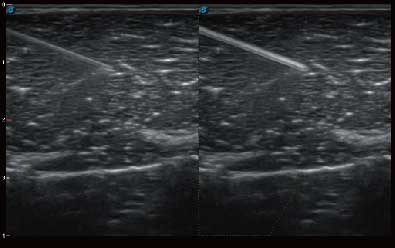

结合哈哈体育官网超宽频带探头技术优势,能够更好地获得高分辨力与高穿透力的平衡,保证图像质量,为临床诊断保驾护航。

微米成像技术提升了对组织斑点噪声信号的抑制能力,并进一步强化边界信息,从而获得清晰图像。